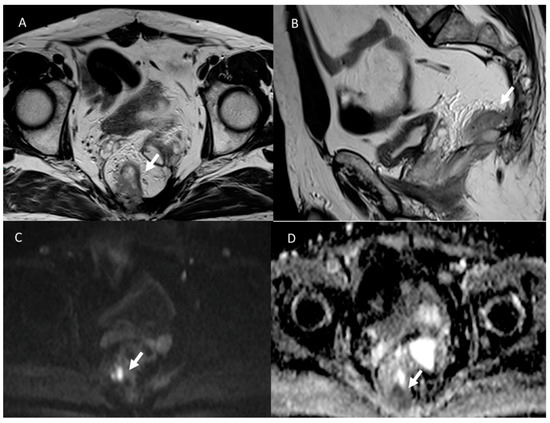

3.7. Local Recurrence

- Molinelli, V.; Angeretti, M.G.; Duka, E.; Tarallo, N.; Bracchi, E.; Novario, R.; Fugazzola, C. Role of MRI and added value of diffusion-weighted and gadolinium-enhanced MRI for the diagnosis of local recurrence from rectal cancer. Abdom. Radiol. 2018, 43, 2903–2912. [Google Scholar] [CrossRef]

- Grosu, S.; Schäfer, A.O.; Baumann, T.; Manegold, P.; Langer, M.; Gerstmair, A. Differentiating locally recurrent rectal cancer from scar tissue: Value of diffusion-weighted MRI. Eur. J. Radiol. 2016, 85, 1265–1270. [Google Scholar] [CrossRef]

- Lambregts, D.M.; Lahaye, M.J.; Heijnen, L.A.; Martens, M.H.; Maas, M.; Beets, G.L.; Beets-Tan, R.G. MRI and diffusion-weighted MRI to diagnose a local tumour regrowth during long-term follow-up of rectal cancer patients treated with organ preservation after chemoradiotherapy. Eur. Radiol. 2016, 26, 2118–2125. [Google Scholar] [CrossRef] [PubMed]

- Colosio, A.; Soyer, P.; Rousset, P.; Barbe, C.; Nguyen, F.; Bouché, O.; Hoeffel, C. Value of diffusion-weighted and gadolinium-enhanced MRI for the diagnosis of pelvic recurrence from colorectal cancer. J. Magn. Reson. Imaging 2014, 40, 306–313. [Google Scholar] [CrossRef] [PubMed]